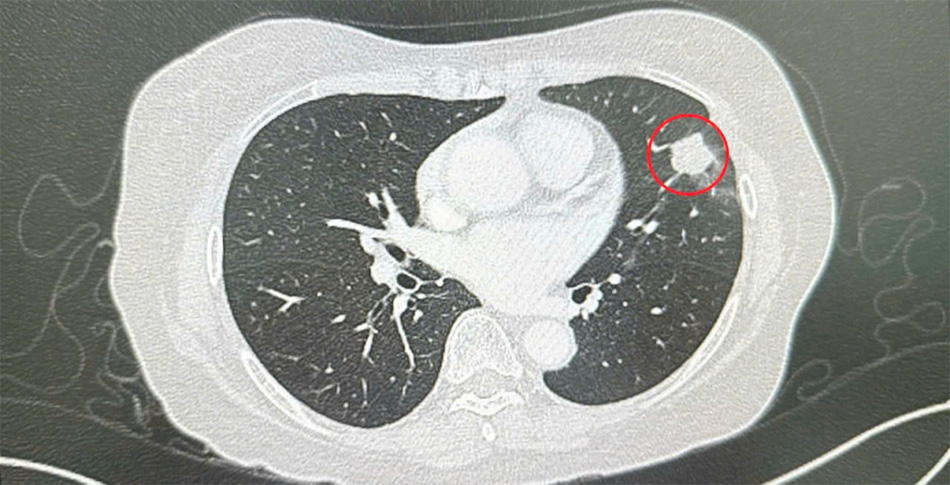

Thạc sĩ, Bác sĩ CKII Lương Ngọc Trung – Trưởng khoa Phẫu thuật Mạch máu, Lồng ngực và Can thiệp nội mạch Bệnh viện FV khám và tư vấn cho chị Nga. Trên phim chụp cho thấy phổi của chị có một đốm mờ hơn 2 cm. “Theo hướng dẫn của Hiệp hội Ung thư, nốt phổi này là tổn thương cần được theo dõi cẩn trọng và xử lý phù hợp”, bác sĩ Trung nhận định. Anh tỉ mỉ phân tích từng khả năng có thể xảy ra và những phương án cho từng khả năng đó để bệnh nhân và gia đình hiểu rõ.

Hình chụp CT ngực với tổn thương ung thư thùy trên phổi trái